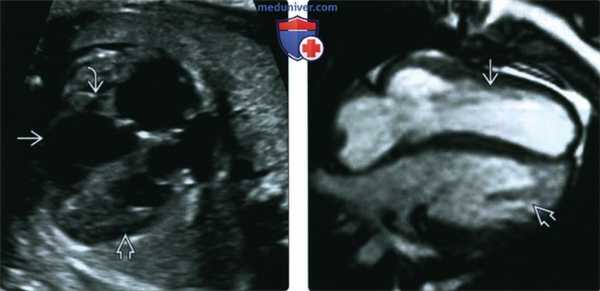

(Слева) УЗИ. ВКТМА. Морфологически ЛЖ (гладкие стенки) находится кпереди от морфологически ПЖ (повышенная трабекулярность). Фиброзные тяжи от АВ-клапана И идут только к свободной стенке сердца, что является отличительной чертой ЛЖ.

(Справа) МРТ новорожденного, четырехкамерный срез. Определяется сходная картина ВКТМА - спереди расположен гладкостенный ЛЖ, а сзади - ПЖ с более выраженной трабекулярностью.